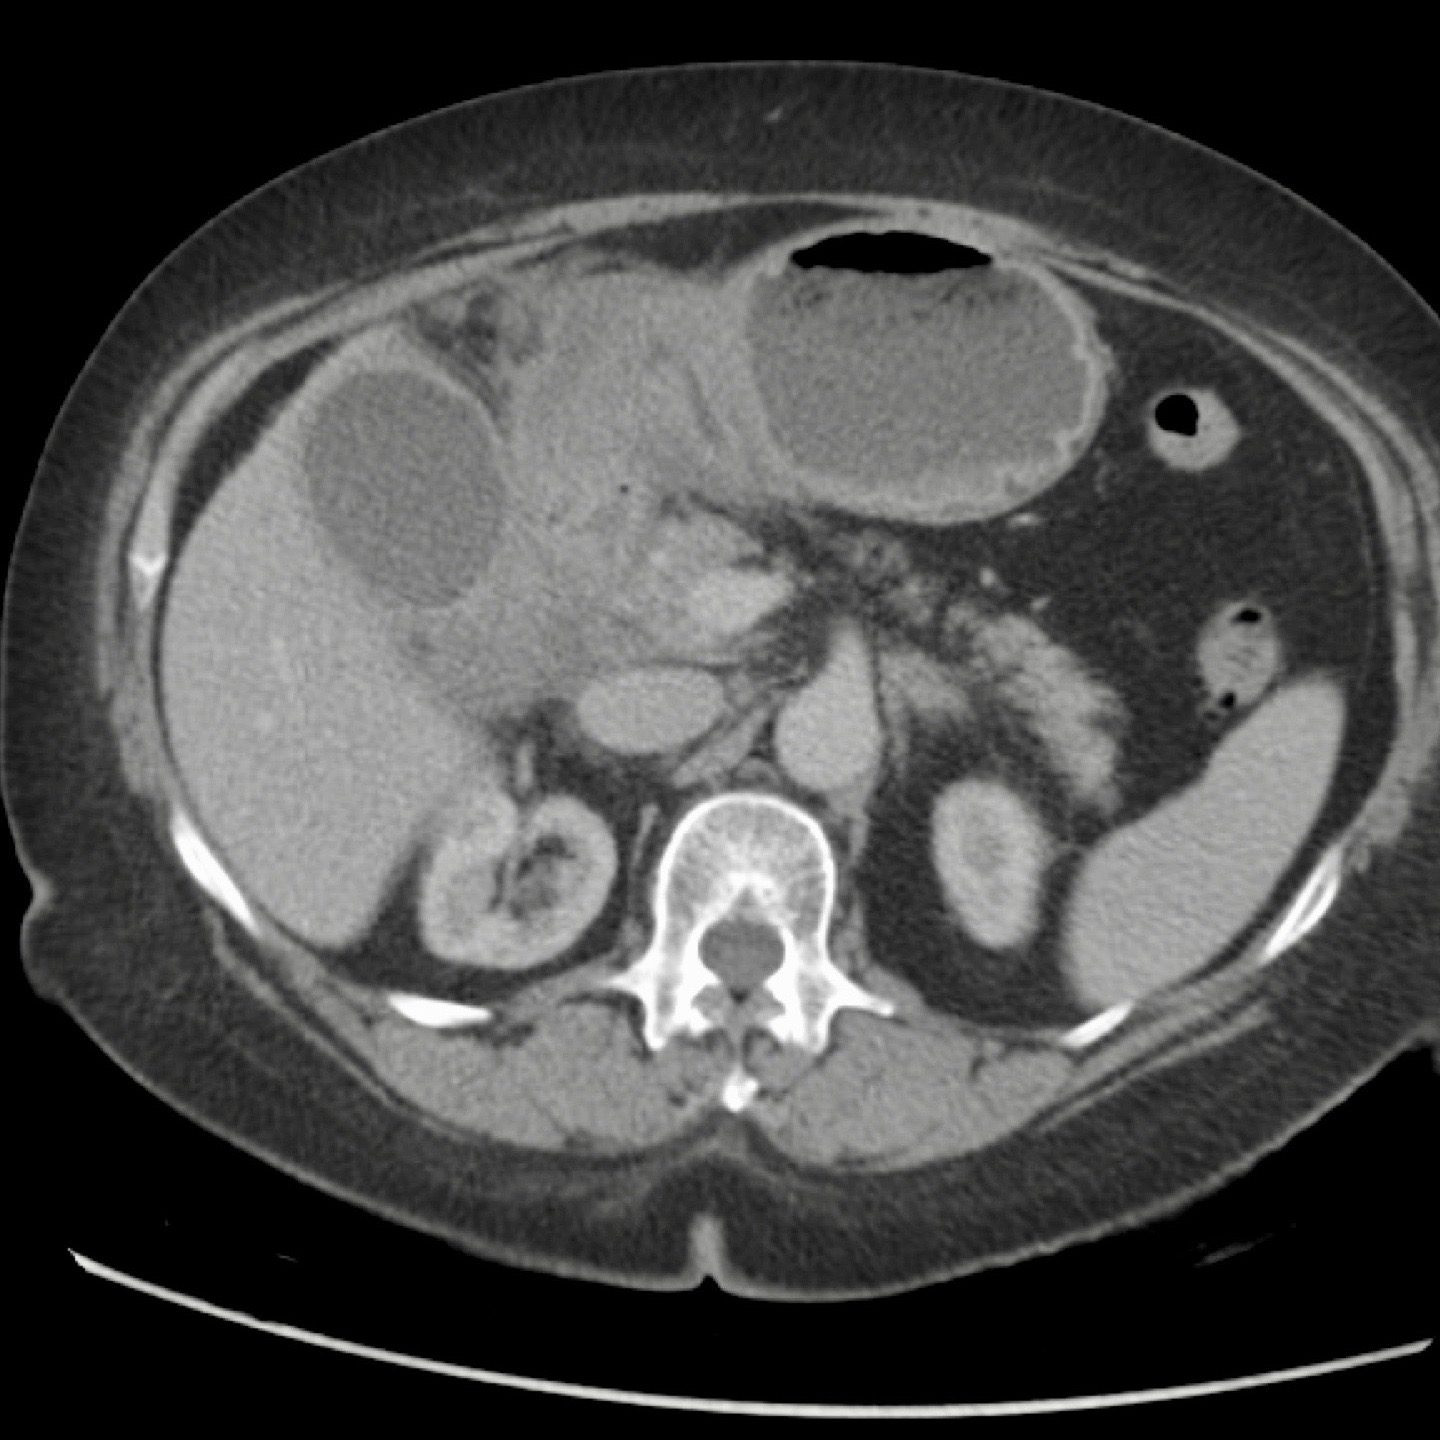

CT trong viêm túi mật cấp

CT có thể rất hữu ích trong các trường hợp siêu âm không cho kết quả chẩn đoán.

Đây là hình ảnh của một bệnh nhân béo phì với đau hạ sườn phải cấp tính trong 6 giờ. CRP 2.

Siêu âm cho thấy túi mật lớn có bùn mật, không quan sát thấy sỏi.

Việc ấn vào túi mật không đáng tin cậy do vị trí cao dưới cung sườn phải.

Không có bất thường siêu âm nào khác.

CT thực hiện cùng ngày cho thấy túi mật lớn với chỉ những thay đổi quanh túi mật kín đáo và không có nguyên nhân nào khác giải thích cho các triệu chứng.

Ngày hôm sau CRP là 105 và CT không tiêm thuốc cản quang lặp lại cho thấy quầng mờ xung quanh túi mật.

Phẫu thuật tiếp theo xác nhận viêm túi mật cấp giai đoạn sớm do sỏi nhỏ trong ống túi mật.